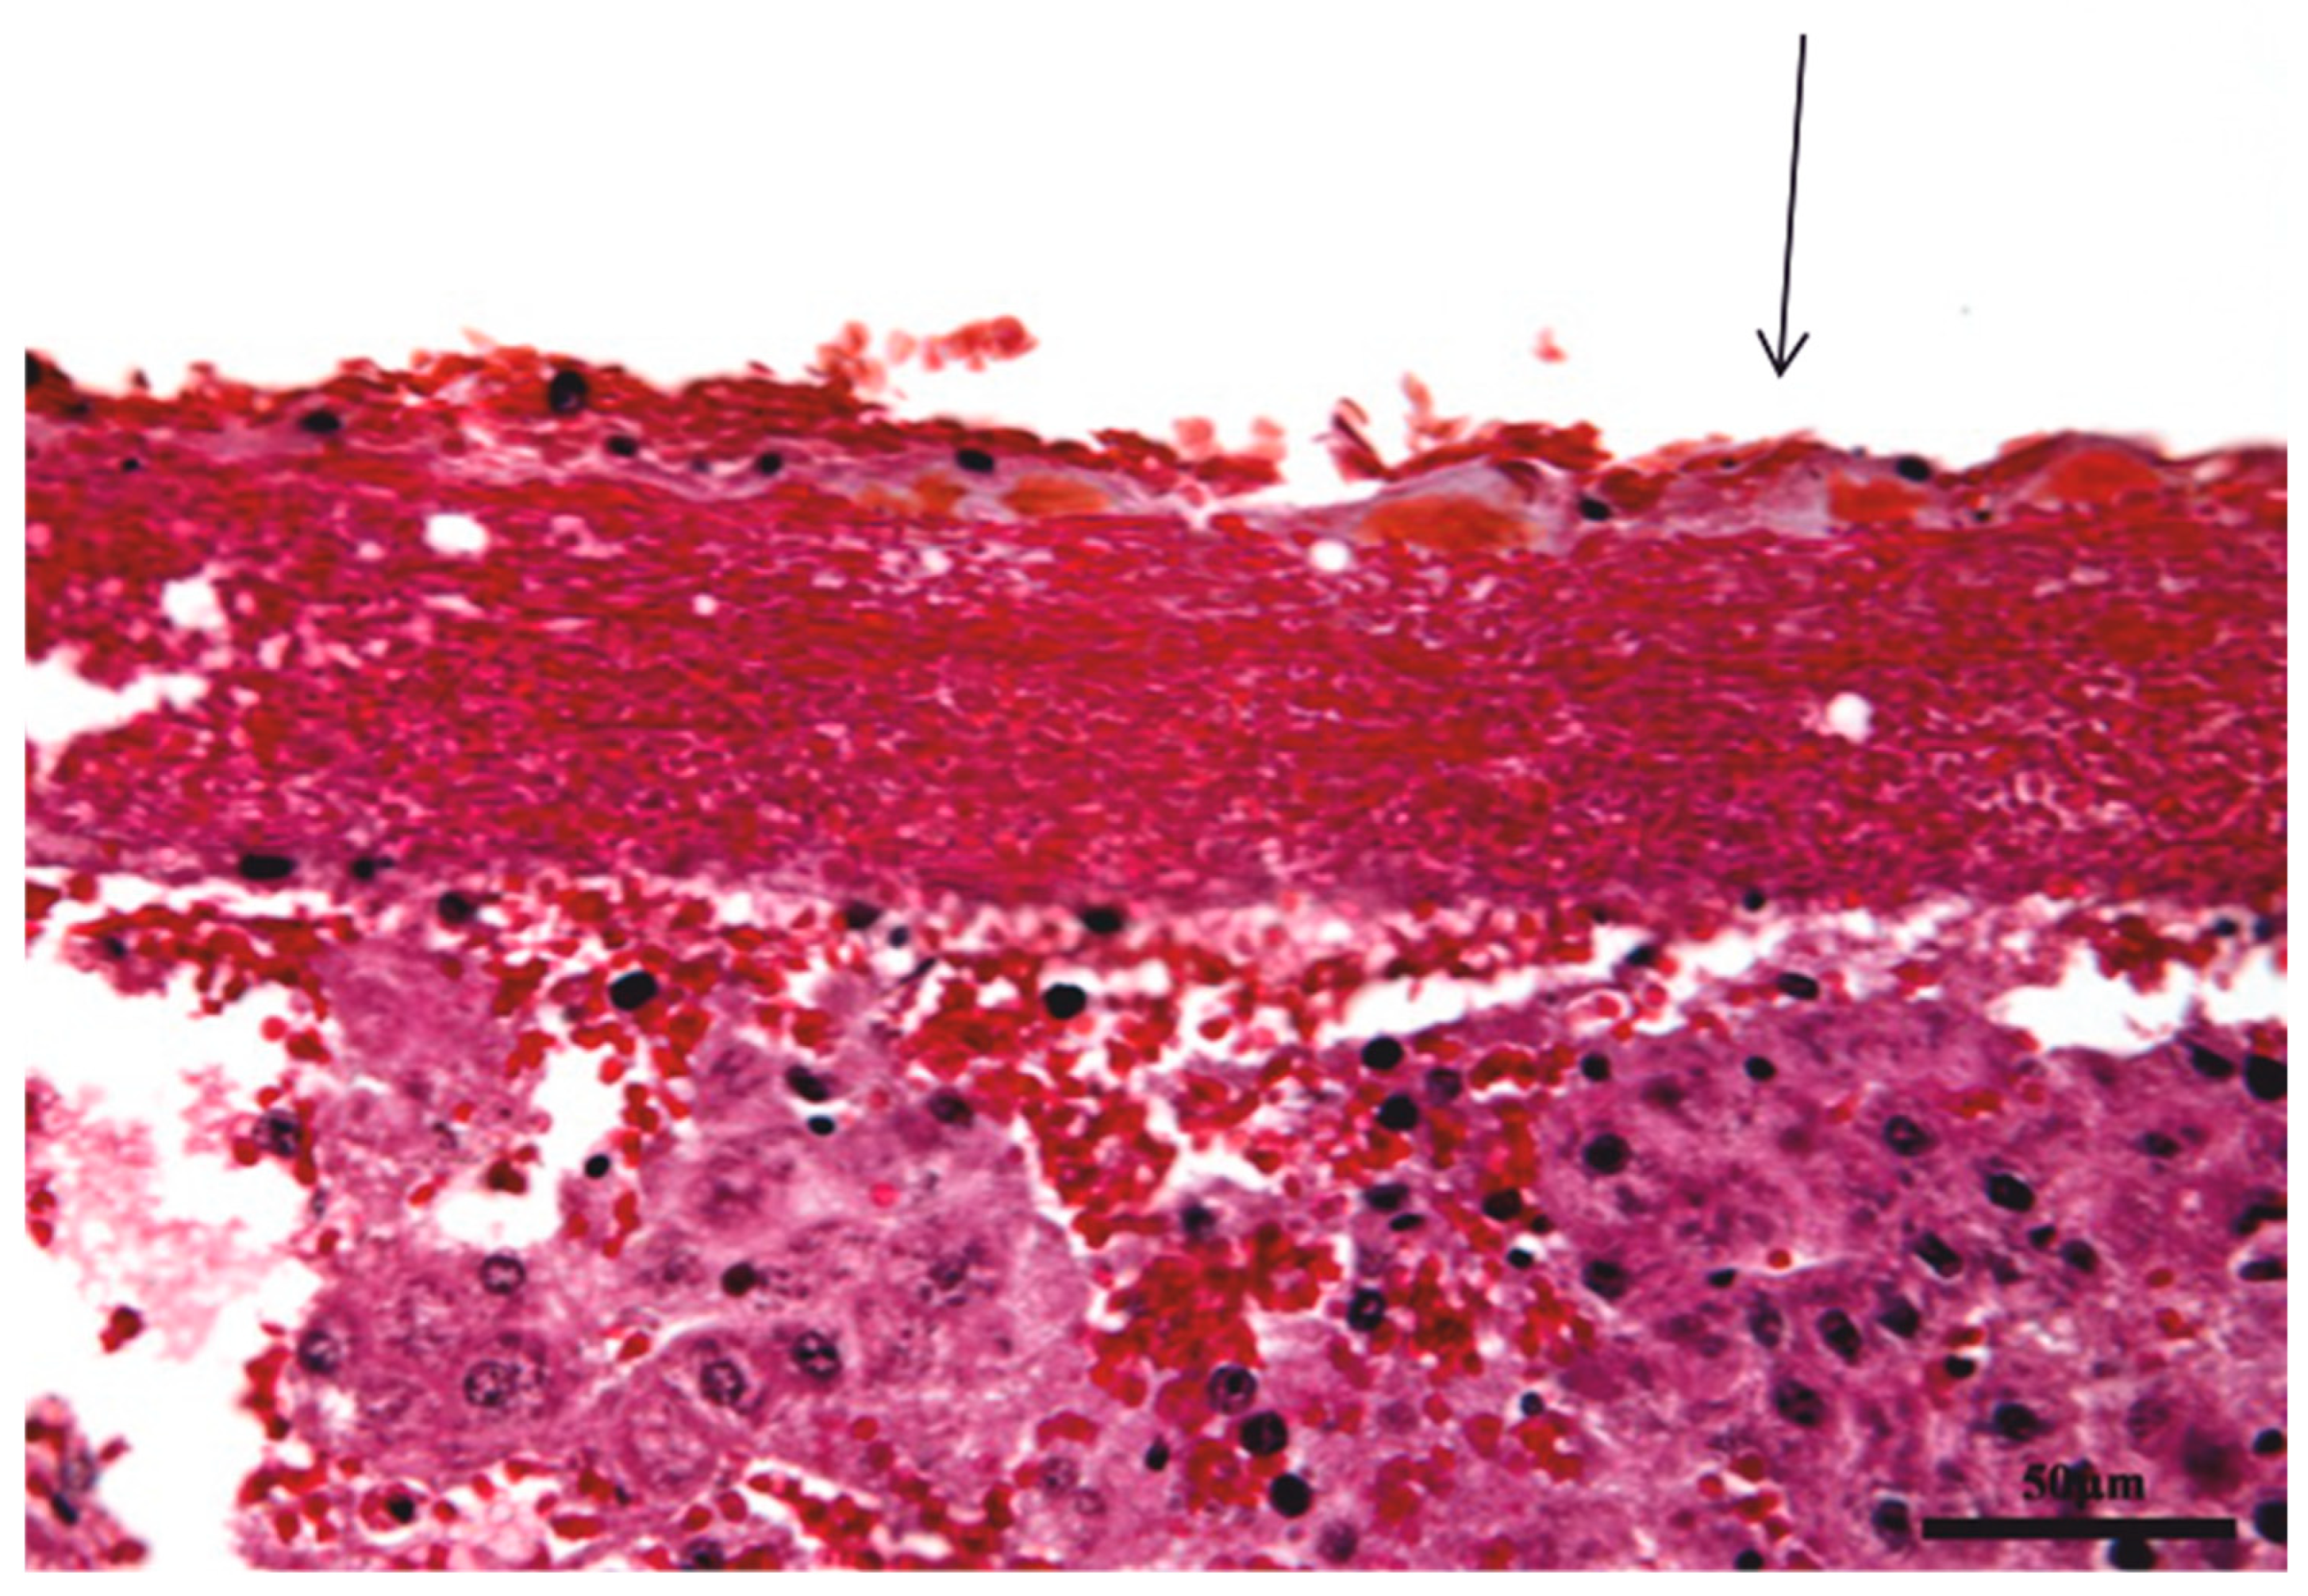

3.1. Histopathologic Results